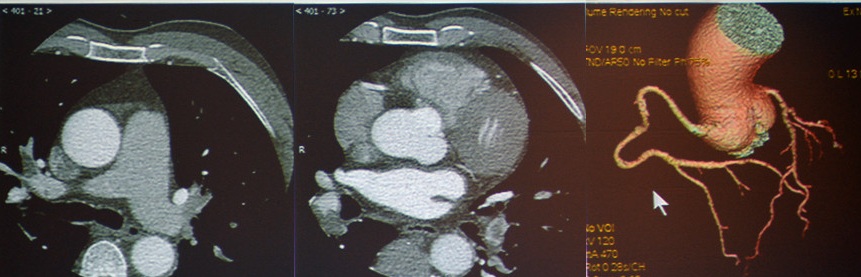

急性主动脉综合征:包括主动脉夹层、壁间血肿、穿透性溃疡。TRO可发现主动脉夹层的真假腔和内膜片。

图8 主动脉夹层Stanford A